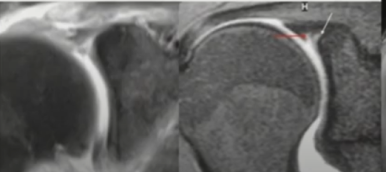

MRI

- SLAP은 MRI상에서 type별로 아래와같이 관찰될 수 있습니다.

▶ 정상 변이(Normal variant)

- 이때 주의할 것은 Sublabral recess는 정상 변이로서, 즉 정상적으로 마치 SLAP처럼 관찰될 수 있다는 것을 알아야 SLAP으로 오진하지 않을 수 있습니다.

- 관절와순이 이두근건에 부착돼있고, 연골부착부가 떨어진 상태로 Nomal claft가 생기면서 관절액이 그 사이를 비집고 들어가 있는 형태입니다.

- Claft는 Smooth 하고, 연골 쪽으로 향해있습니다. 이 claft의 직경은 대부분 5mm보다 적습니다.